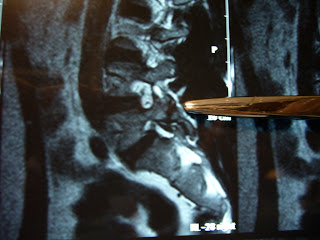

His X-Ray shows a slight lucency posteriorly at L5 where the stress crack is located, but it is hard to see.

The MRI sagital reconstruction shows the small crack in the posterior elements, pointed out with the probe in the picture. Often these cracks are very hard, if not impossible to see on MRI, but might be picked up better on CT scan. “SPECT bone scans”, not just “whole body” bone scans are very sensitive for picking up even non-displaced or unilateral (one-sided) fractures.